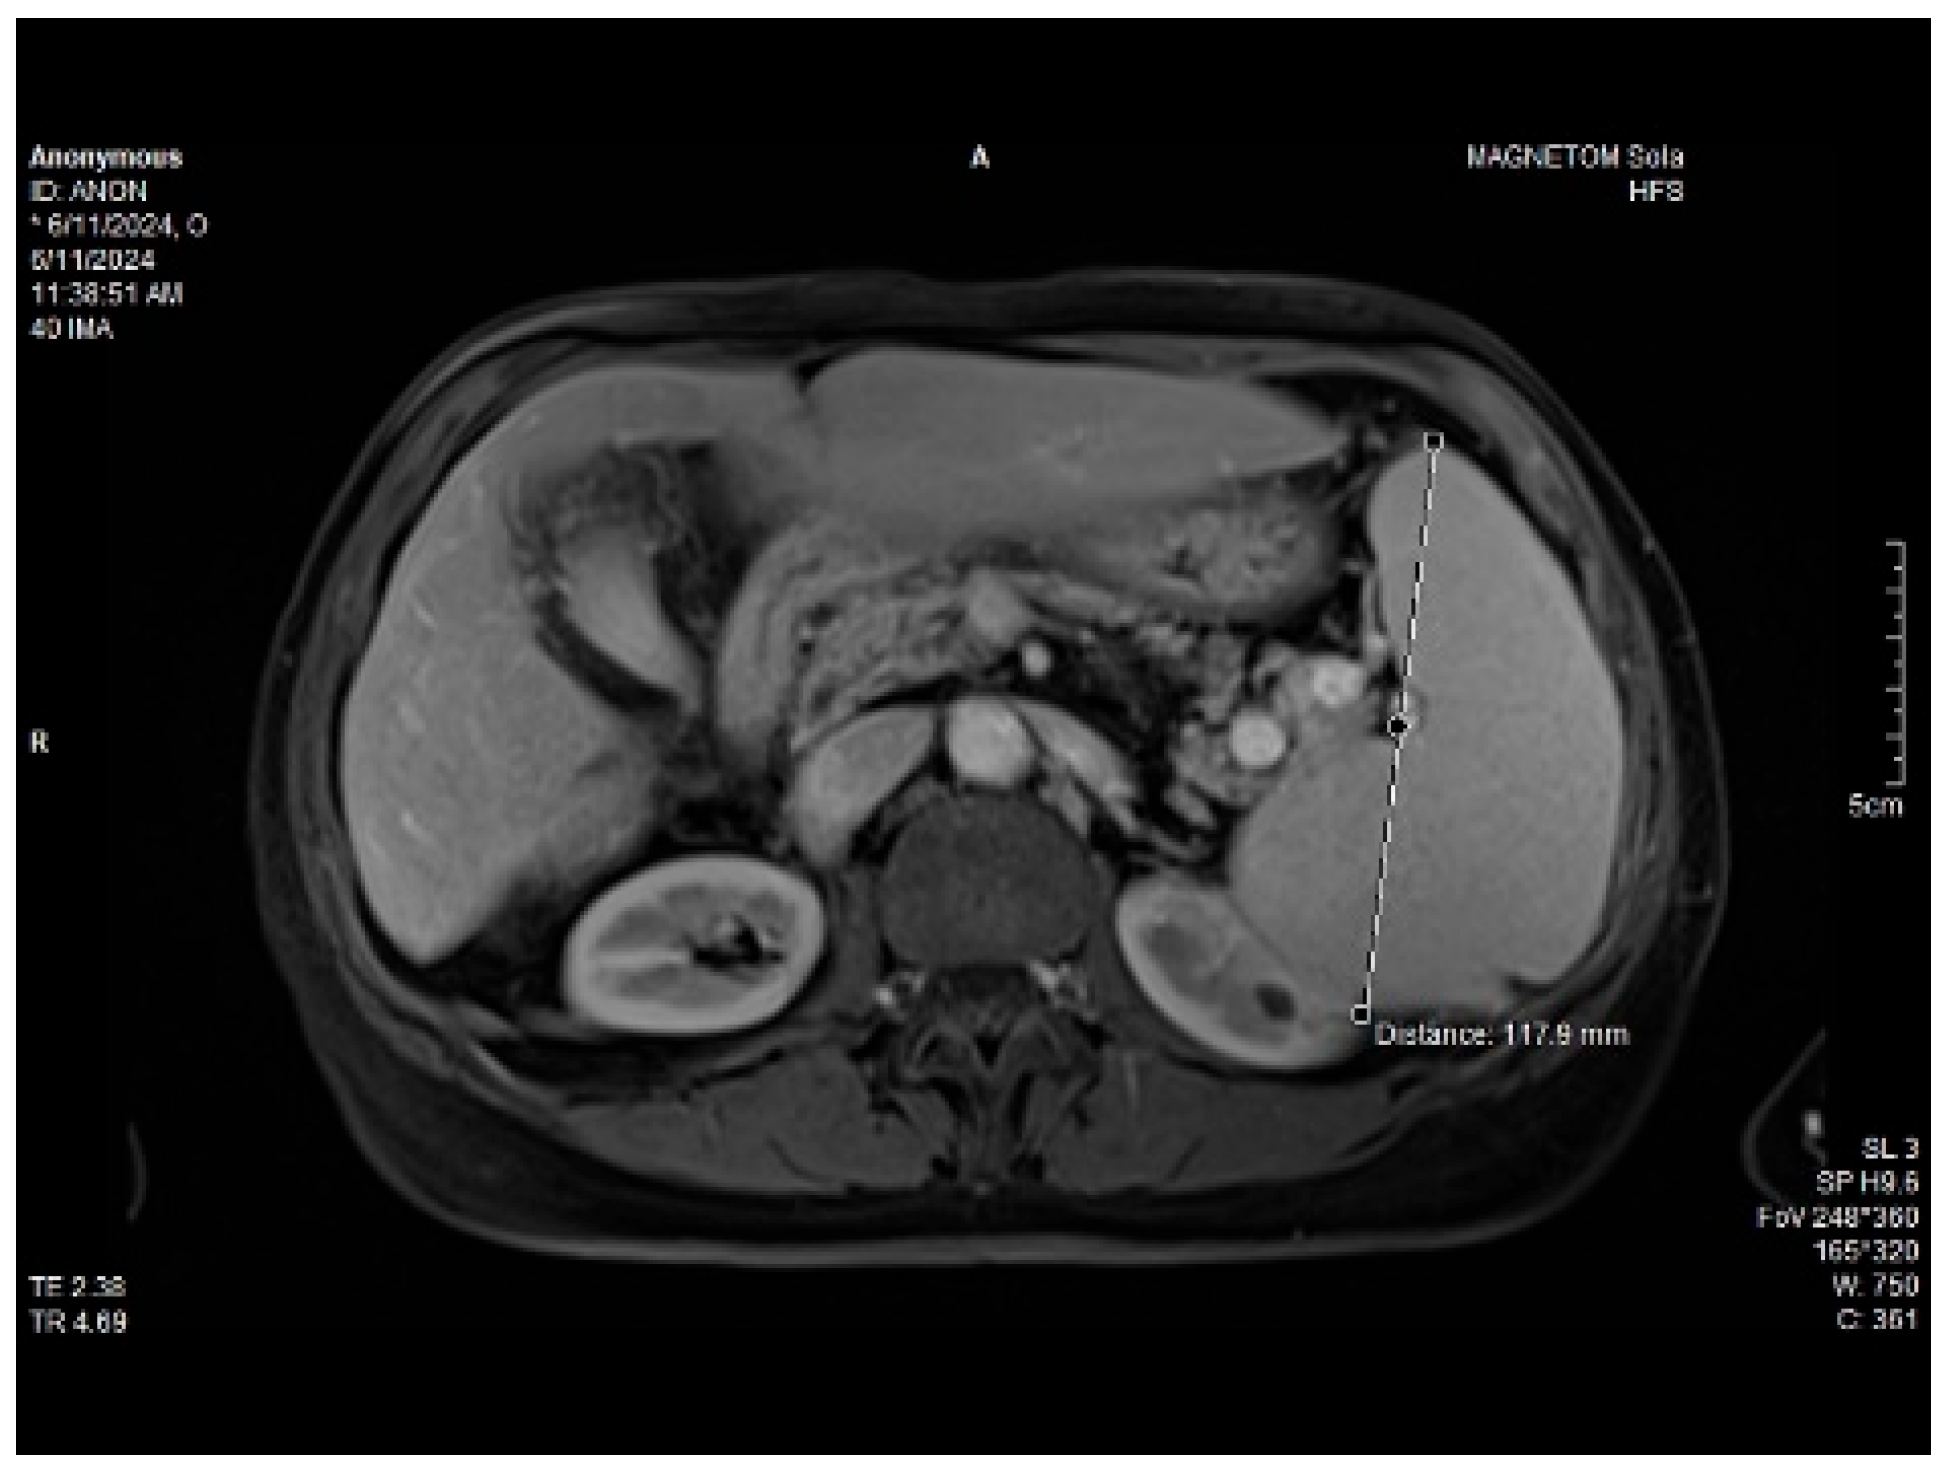

Abdominal MRI study confirmed the hepato-splenomegaly, ascites and the patency of the portal vein system. In addition, small veno-portal shunts were highlighted at the periphery of both hepatic lobes. Various MRI features are depicted in Figure 6, Figure 7, Figure 8 and Figure 9.

Figure 6. MRI featuring perihepatic and perisplenic ascites.